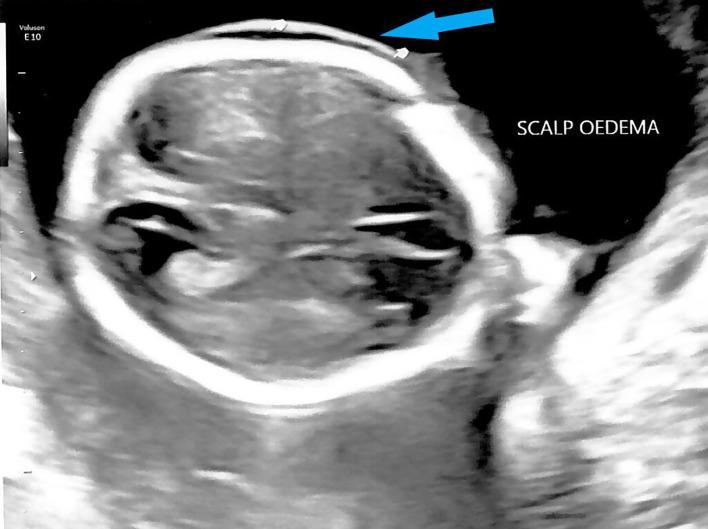

Hemoglobin (Hb) Bart's hydrops fetalis is the most severe form of α-thalassemia and is usually inherited in an autosomal recessive manner. We report a case of Hb Bart's hydrops fetalis due to uniparental disomy of chromosome 16. Antenatal screening showed a low maternal mean corpuscular volume (MCV), while paternal MCV was normal. The fetus was found to have a thickened nuchal translucency during first trimester screening for Down's syndrome. Mid-trimester fetal anomaly ultrasound scan showed fetal cardiomegaly with pericardial effusion, scalp edema, ascites and an elevated middle cerebral arterial peak systolic velocity (MCA PSV). Multiplex polymerase chain reaction (PCR) on DNA from amniocentesis showed that the fetus was homozygous for South East Asian (SEA) type 2 α-globin gene deletion. Chromosome microarray (CMA) showed two regions of absence of heterozygosity (AOH) on the terminal p and q arm of chromosome 16. The rare occurrence of Hb Bart's hydrops fetalis caused by maternal uniparental disomy should be considered in cases of fetal hydrops even in cases where paternal MCV is normal.

血红蛋白(Hb)巴特胎儿水肿综合征是α地中海贫血最严重的形式,通常以常染色体隐性方式遗传。我们报告了一例因16号染色体单亲二体导致的血红蛋白巴特胎儿水肿综合征病例。产前筛查显示母亲平均红细胞体积(MCV)较低,而父亲的MCV正常。在孕早期唐氏综合征筛查中,发现胎儿颈部半透明层增厚。孕中期胎儿畸形超声扫描显示胎儿心脏肥大并伴有心包积液、头皮水肿、腹水以及大脑中动脉收缩期峰值流速(MCA PSV)升高。对羊水穿刺获得的DNA进行多重聚合酶链反应(PCR)显示,胎儿为东南亚(SEA)型2α珠蛋白基因缺失纯合子。染色体微阵列(CMA)显示16号染色体末端p和q臂上有两个杂合性缺失(AOH)区域。即使父亲的MCV正常,在胎儿水肿的病例中也应考虑由母亲单亲二体导致的罕见血红蛋白巴特胎儿水肿综合征。